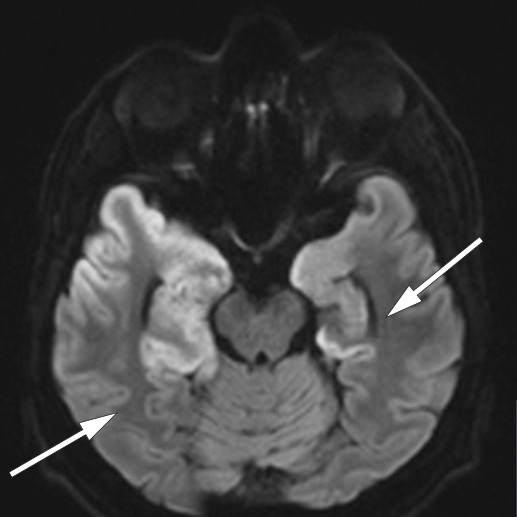

Denne viste patologisk langsom bakgrunnsaktivitet og utbrudd av deltaaktivitet i temporale regioner. Funnet var forenlig med encefalitt (6, 7). MR-undersøkelse av hodet, som ble utført seks dager etter innleggelsen, viste utbredte forandringer temporalt, inkludert i hippocampus, hvilket er typisk for herpesencefalitt (8) (figur 2, figur 3a).

En uke etter oppstart med immunglobulinbehandling ble det bekreftet høyt titer av antistoff mot NMDA-reseptor i pasientens spinalvæske. En ny cerebral MR-undersøkelse tatt fire uker etter den første, viste økende høysignalforandringer temporalt bilateralt. Dette funnet er ikke spesifikt for verken herpesencefalitt eller autoimmun encefalitt (11).

Tilstanden stabiliserte seg etter noe tid, og man forsøkte rehabilitering i flere omganger, men pasienten gjenvant aldri tilstrekkelig funksjon til å kunne bo hjemme. Han bor nå i omsorgsbolig med stort oppfølgingsbehov. En ny MR-undersøkelse 4,5 måneder etter symptomdebut viste omfattende skade i temporallapper (figur 3b).

Hos vår pasient var det nok allikevel den virale encefalitten som ga størst permanent skade (figur 3a og b).